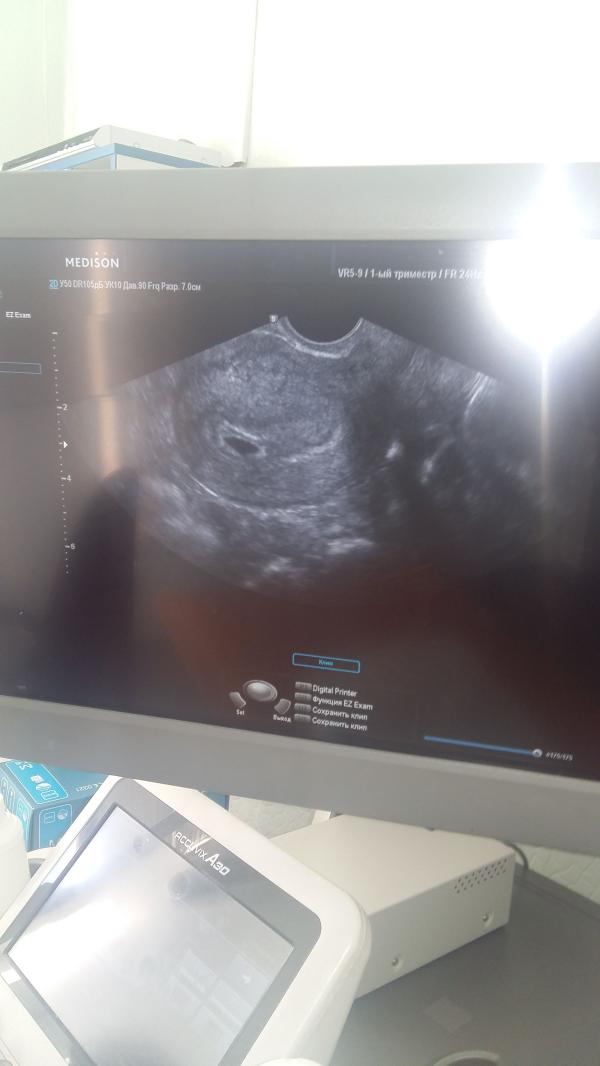

На фото наше первое узи 😊😍

Сегодно с утра сходила сделала полноценное трансвагинальное узи. В итоге по М должно быть 6 недель беременности, а по узи выходит не больше 4. как так то? 😦 вообще тогда ничего не понимаю...что они там, как они считают. Я Уже совсем запуталаст.